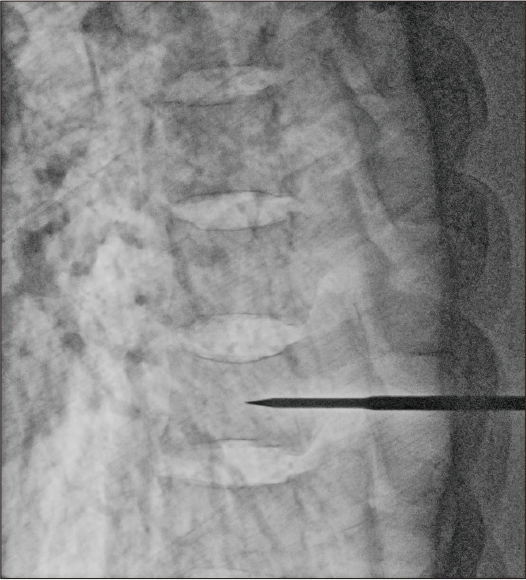

After applying Dynamic processing

Dose: 8.4mA